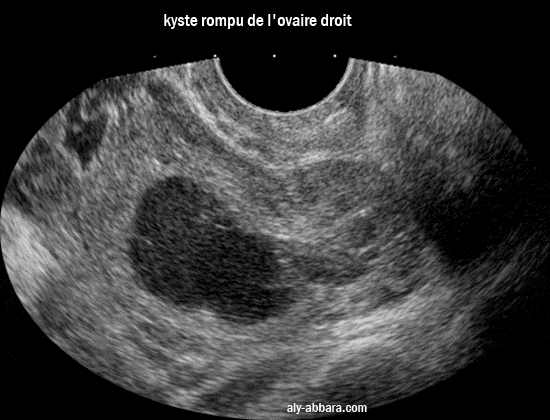

kyste rompu de l'ovaire droit

Cette rupture est associée à un hémopéritoine restant localisé dans le petit pelvis